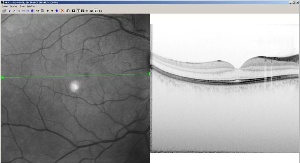

The Spectralis HRA+OCT is 100 times

faster than time domain OCT offering greater detail and revealing

previously unseen retinal structures. (Graphic: Business Wire) |

The new device scans the retina 100 times faster than older existing

technology known as time domain OCT. The Spectralis HRA+OCT is a spectral

domain system, sometimes called fourier domain, which scans the retina at

40,000 scans per second, creating highly detailed images of the structure of

the retina. Because the OCT and Heidelberg Retina Angiograph (HRA) images

are captured simultaneously, the clinician can be assured of the exact

location of the area of interest and can correlate the outer visible retina

structure with the internal structure.